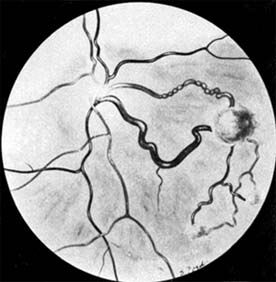

Retinoblastomas may exhibit outward (exophytic) or inward (endophytic) growth-either or both. The latter then extend into the vitreous (Figure 10-33). Both types gradually fill the eye and extend through the optic nerve to the brain and, less commonly, along the emissary vessels and nerves in the sclera to the orbital tissues. Occasionally, they grow diffusely in the retina, discharging malignant cells into the vitreous or anterior chamber, thereby producing a pseudoinflammatory process and mimicking retinitis, vitritis, uveitis, or endophthalmitis. Microscopically, most retinoblastomas are composed of small, closely packed, round or polygonal cells with large, darkly staining nuclei and scanty cytoplasm. They sometimes form characteristic Flexner-Wintersteiner rosettes, which are indicative of photoreceptor differentiation. Degenerative changes are frequent, accompanied by necrosis and calcification. A few will spontaneously resolve.

Figure 10-33

Figure 10-33: Endophytic retinoblastoma.

Enucleation is the treatment of choice for large retinoblastomas. Eyes with smaller tumors can be effectively treated with plaque or external beam radiotherapy (Figure 10-34), cryotherapy, or photocoagulation. Chemotherapy is being used to reduce the size of large tumors prior to other types of therapy and occasionally as the sole form of therapy. It is also used to treat tumors that have extended into the brain, orbit, or distally and may be used after enucleation in patients at high risk for such widespread disease.

Figure 10-34

Figure 10-34: Retinoblastoma after radiotherapy.